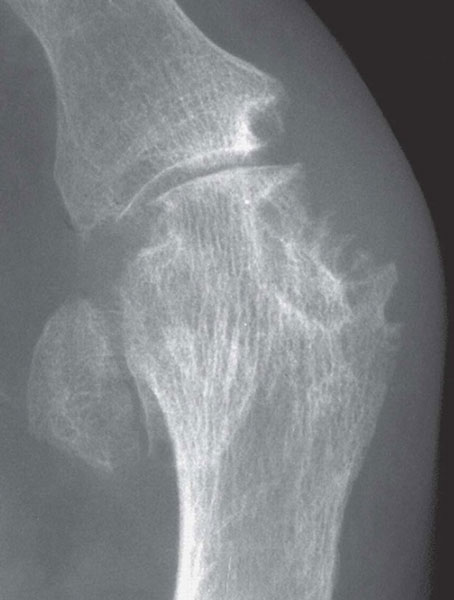

Although radiographic changes are usually a late feature, occasionally they may be seen at presentation, see figure 1. The most common presentation is a gout flare, characterised by acute onset of one, or occasionally more, hot, red, swollen joints which are extremely painful and exquisitely tender. Flares reach a peak in just 12-24 hours. Although any joint can be affected, most flares affect joints in the feet, knees, hands or elbows. Involvement of the first metatarso-phalangeal joint, termed podagra (seizing the foot), is very characteristic, see figure 2.

Radiographs do not often show characteristic features of gout until late in the disease, but joint ultrasound usually demonstrates characteristic features (microtophi in synovium and periarticular sites, and crystal deposits in superficial articular cartilage producing a parallel double contour line with subchondral bone) at first presentation in multiple peripheral sites, not just the presenting symptomatic joint.